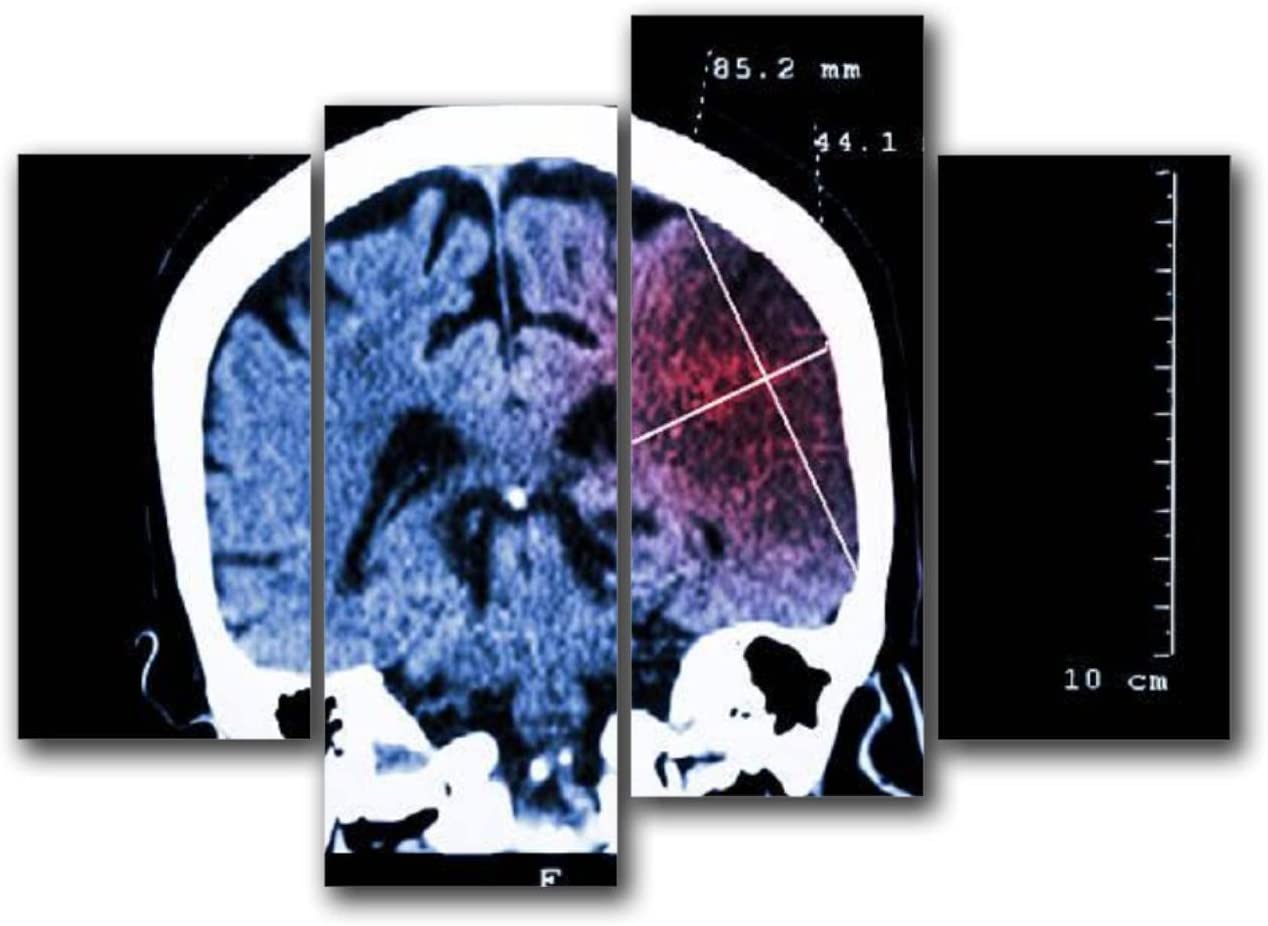

1. 신속한 평가 및 진단: 뇌경색 초기증상과 징후를 신속하게 인식하는 것은 적시에 개입하고 환자 결과를 개선하는 데 필수적입니다. 의료 전문가는 NIHSS(National Institutes of Health Stroke Scale)와 같은 도구를 사용하여 잠재적인 뇌경색 환자를 신속하게 평가하고 컴퓨터 단층 촬영(CT) 스캔 또는 자기 공명 영상(MRI)을 포함한 진단 테스트를 시작하여 진단을 확인하고 유형을 결정해야 합니다.

• 출혈성 뇌졸중(뇌 내 출혈로 인해 발생)의 치료는 출혈 조절, 두개골 내 압력 감소, 근본 원인 해결에 중점을 둡니다. 여기에는 혈압을 조절하거나 항응고를 역전시키거나 뇌 부종을 줄이기 위한 약물이 포함될 수 있습니다. 어떤 경우에는 혈액을 제거하거나 손상된 혈관을 복구하기 위해 외과적 개입이 필요할 수 있습니다.